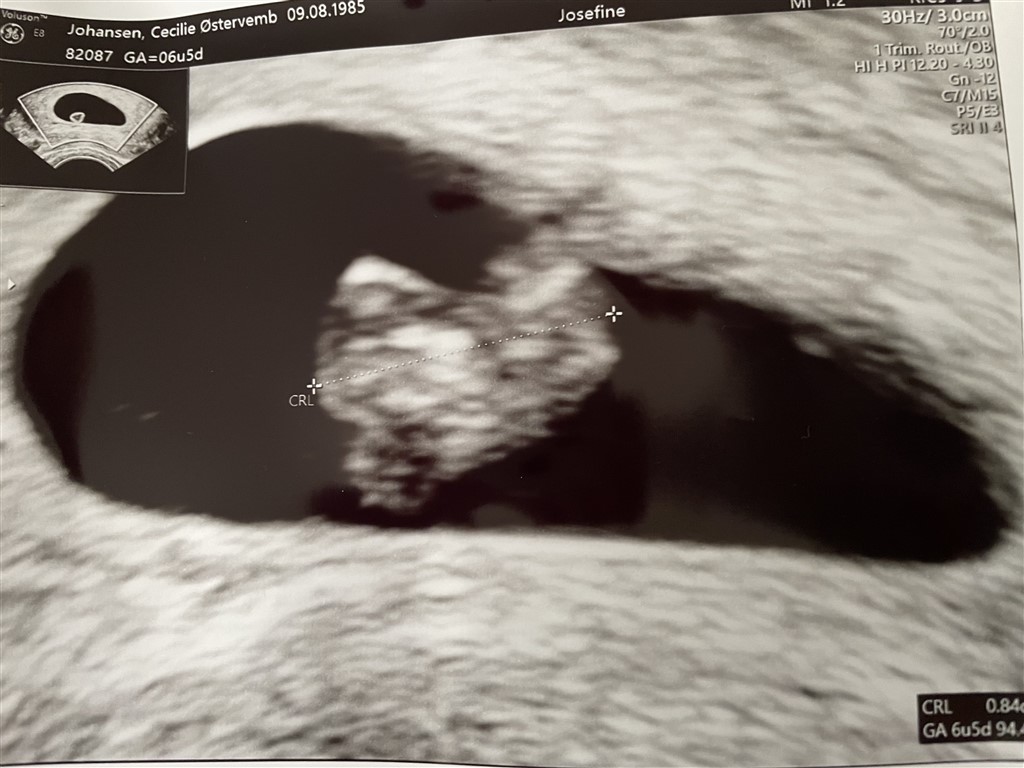

Jeg var til scanning 6+5 og her er mit scanningsbillede  der kunne ses hjerteblink med et hjerte der netop var begyndt at slå, så du kan være heldig at se hjerteblink, men det kan også være det lige er lidt for tidligt

Vedhæftede fotos (klik for at se i fuld størrelse)